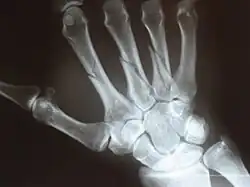

Wrist and hand injury

Wrist mobility is often restricted due to inflammation of the forearm muscles as they contract and tighten due to injury.[2] Most wrist dislocations occur between the capitate and the lunate.[17][18] Carpal fractures are caused by falling on an outstretched hand the wrist is hyper-extended in ulnar deviation with a component of rotation.[18] Swelling of the Median nerve tissue leads to nerve entrapment ultimately resulting in restriction of movement, other symptoms include; pain, numbness and weakness.[1] DeQuervain's Tenosynovitis is a form of tendinitis of the muscles that move the thumb.[2]